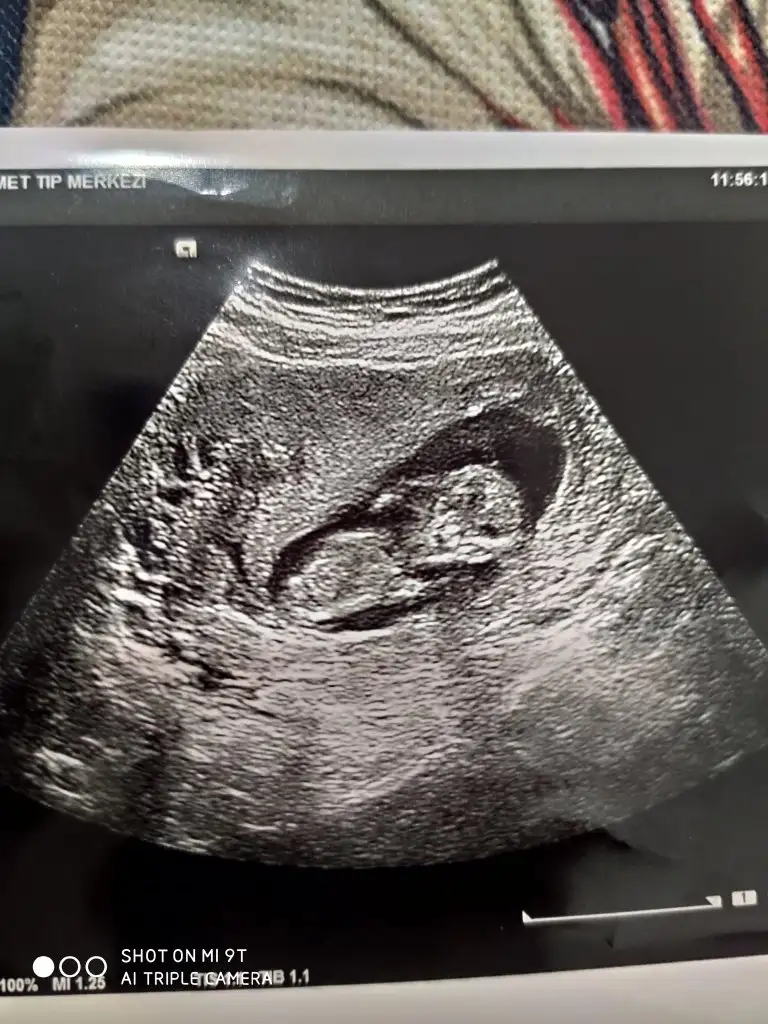

Erkek12 haftalık bana da bakabilir misiniz![]()

Diğer taraftaki konumda yazdim erkek gibi sanki tekrar USG paylasin12 haftalık bana da bakabilir misiniz![]()

12 haftalık USG bu çok teşekkür ederimDiğer taraftaki konumda yazdim erkek gibi sanki tekrar USG paylasin